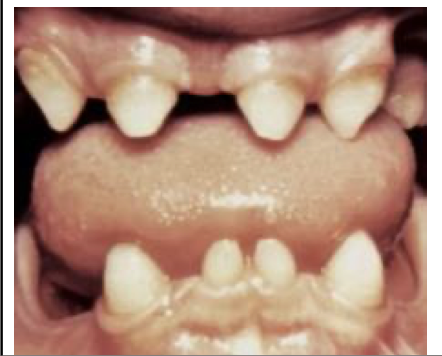

Ectodermal Dysplasia

X-Linked Recessive

Common Signs:

* Missing Teeth

* Multiple sharp pointed teeth

* Hypoplastic hair or nails

How well did you know this?